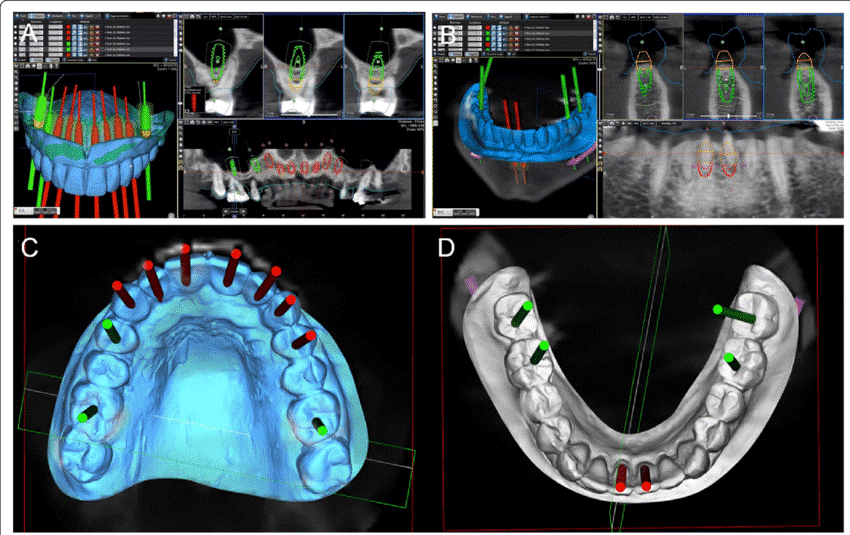

1. Static Guided Surgery: The Role of 3D-Printed Surgical Guides

- Uses pre-planned digital implant placement data to fabricate custom 3D-printed surgical guides.

- Guides assist in precise angulation and depth control, reducing operator error.

- Requires CBCT and intraoral scans, followed by guide fabrication using CAD/CAM technology.

🔹 Advantages:

- High surgical accuracy, especially for multiple implants.

- Cost-effective compared to real-time navigation.

- Shorter surgical time, as the guide ensures rapid drilling execution.

🔹 Limitations:

- Requires additional time for guide fabrication, causing surgical delays.

- No real-time adaptability—if bone quality differs from the plan, modifications cannot be made mid-surgery.